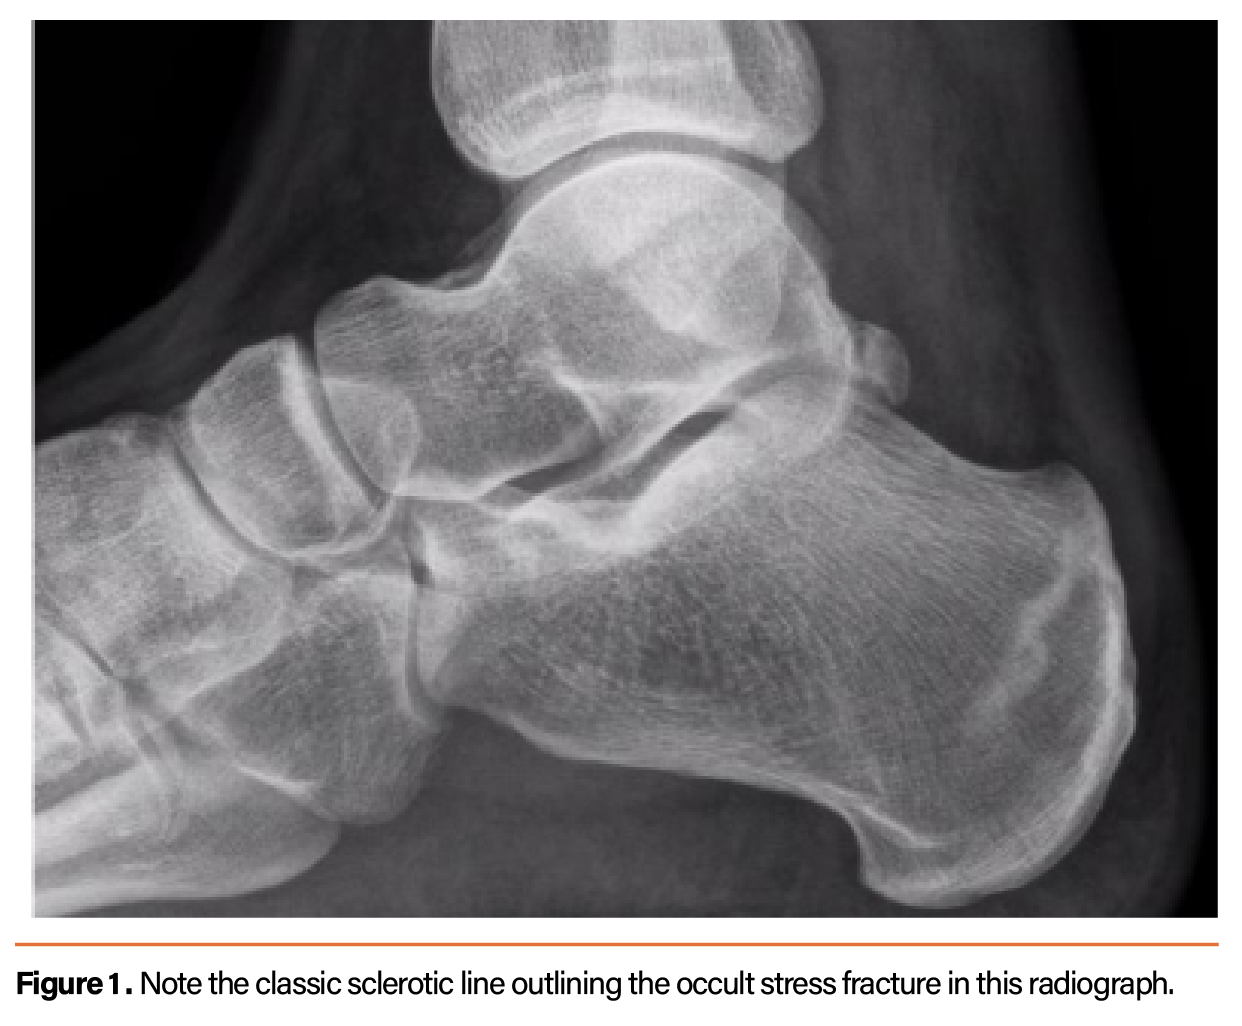

Discover the causes, symptoms, and effective treatment options for bilateral facet arthropathy. Learn how this common spinal condition causes chronic lower back pain and stiffness. Our expert guide explores non-surgical pain management techniques, physical therapy, and lifestyle adjustments to help you regain mobility and improve your quality of life while managing spinal joint inflammation and degeneration.